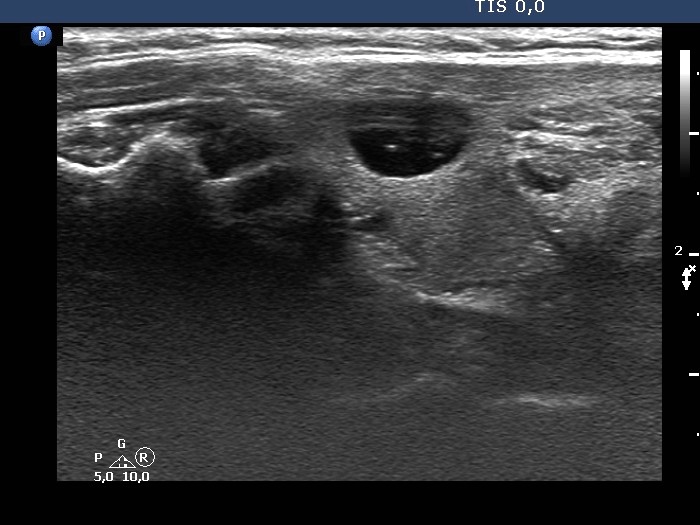

The composition of the nodule - case 142

Examination 3 years later (ultrasonographic picture 11)

Left lobe, another longitudinal scan.